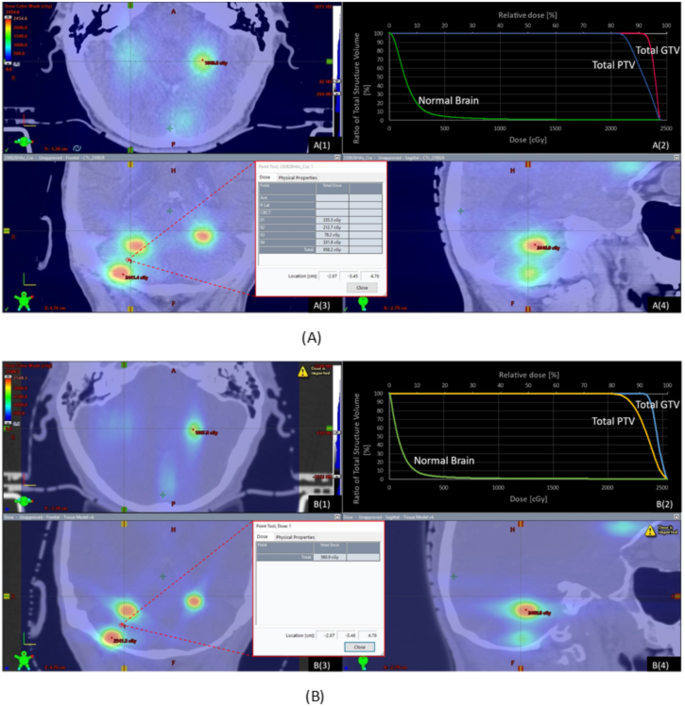

The dosimetric characteristics of VMAT and DCAT can be visualized from a sample plan in Fig. 3 which has a prescription of 20 Gy at 80% isodose line. Comparing the VMAT generated plan (Fig. 3A) against DCAT generated plan (Fig. 3B) shows a more visible dose bridge between individual targets. A wider dose bridge indicates a larger volume of dose spill, so that the normal tissue at the close vicinity of the targets is more likely to be irradiated; The point dose was measured to be 958.2 cGy (VMAT) versus 560.9 cGy (DCAT) at the same location (difference ± 0.1 mm) at the middle of the dose bridges, see Fig. 3. Comparing Fig. 3A(2) and B(2) which contain the cumulative dose volume histograms (cDVH), both VMAT and DCAT saw sharp dose fall-off at PTV and GTV margins with comparably good local control represented by low doses to the normal brain.

Dose distributions of a case with a prescription of 20 Gy at 80% isodose line. (A) Dose distribution of the VMAT plan. A(1): Transversal, Y=–1.38 cm; A(2): cDVH of total PTV, total GTV, and Normal Brain; A(3): Frontal, Z = 4.76 cm; A(4): Saggital, X=–2.79 cm. The point dose at the middle of the dose bridge (location X=-2.97 cm, Y = -3.45 cm, Z = 4.76 cm) was 958.2 cGy. (B) Dose distribution of the DCAT plan. B(1): Transversal, Y=–1.38 cm; B(2): cDVH of total PTV, total GTV, and Normal Brain; B(3): Frontal, Z = 4.76 cm; B(4): Saggital, X=–2.79 cm. The point dose at the middle of the dose bridge (location X=-2.97 cm, Y=-3.46 cm, Z = 4.76 cm) was 560.9 cGy.